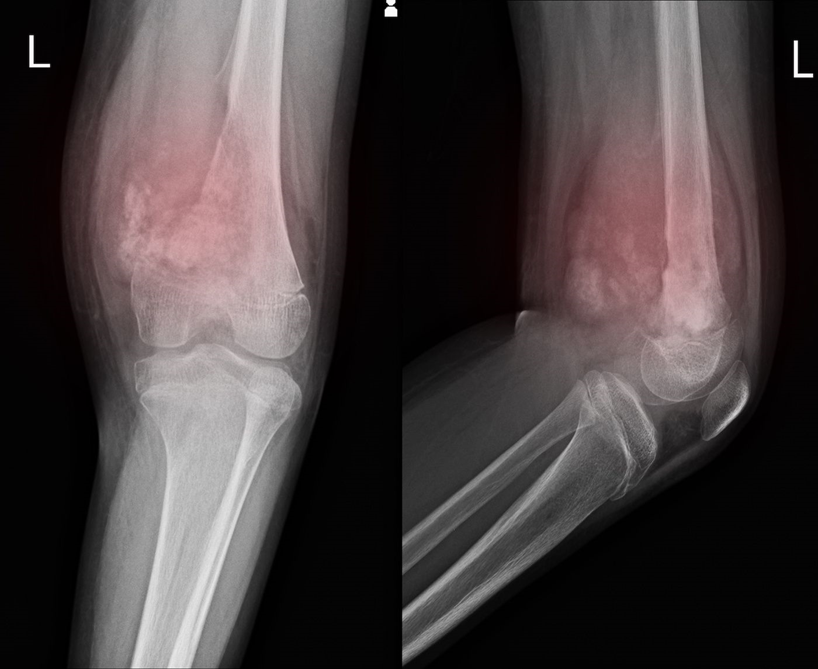

ΠΠ°ΡΠΎ ΡΡΠ»ΠΎ ΡΠ°ΡΠΊΠΎΠΌΠ° Π΅ ΠΌΠ½ΠΎΠ³ΠΎ ΡΡΡΠ΄Π΅Π½ Π·Π° Π΄ΠΈΠ°Π³Π½ΠΎΡΡΠΈΡΠΈΡΠ°Π½Π΅ ΠΈ ΡΠ΅Π½ΡΠ³Π΅Π½ΠΎΠ²ΠΈΡΠ΅ ΡΠ½ΠΈΠΌΠΊΠΈ ΠΈΠ»ΠΈ ΡΡΠ°Π½Π΄Π°ΡΡΠ½ΠΈΡ Π΅Ρ ΠΎΠ³ΡΠ°Ρ Π½Π΅ ΠΌΠΎΠ³Π°Ρ Π΄Π° Π΄Π°Π΄Π°Ρ Π΄Π΅ΡΠΈΠ½ΠΈΡΠΈΠ²Π½Π° Π΄ΠΈΠ°Π³Π½ΠΎΠ·Π°.